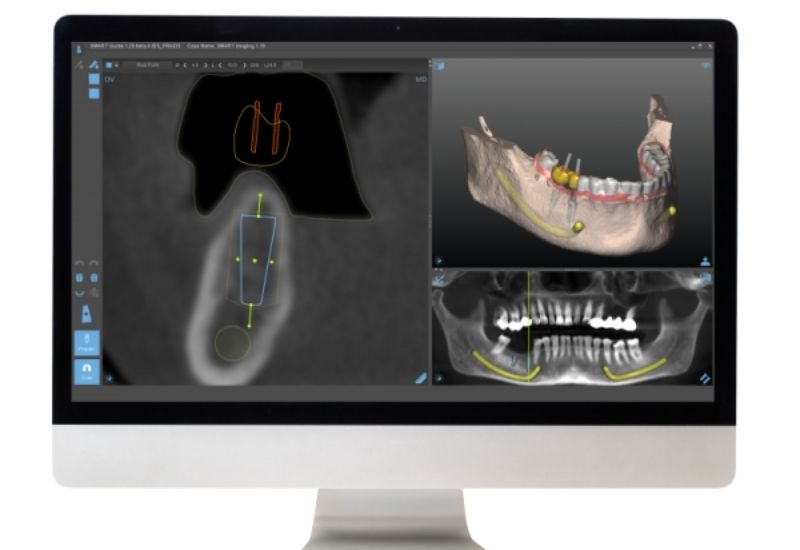

Ezután a CT felvételt és a CBCT sablonról készült felvételt beolvassuk a SMART Guide tervező szoftverébe. Így láthatóvá válik a rendelkezésre álló csontszövet minősége és mennyisége valamint az idegcsatornák és az arcüregek elhelyezkedése is. Ez alapján kiemelkedő pontossággal tudjuk megtervezni az implantátum elhelyezkedését és méretét.